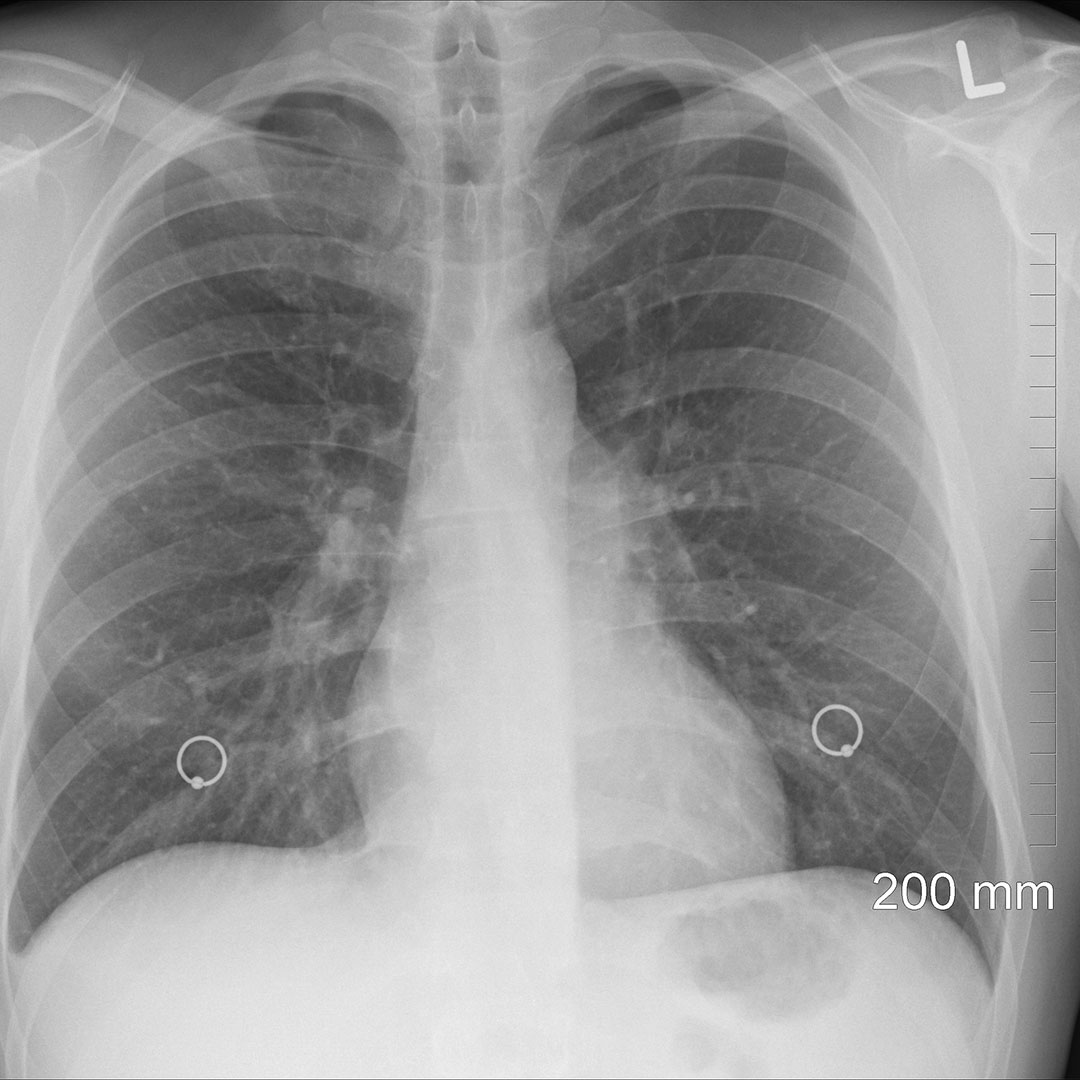

Tumore al polmone, la rivoluzione grazie a un robot come funziona il Giornale Presenta 3636 articoli relativi a: Tumore Ai Polmoni ; Data dell'ultima notizia: Domenica, 9 Marzo 2025 ; Titolo dell'ultima news: Com'è morta Eleonora Giorgi?/ Tumore al pancreas: "Si era esteso a polmoni e cervello: ci ha chiesto di…" Circa l'85% dei casi è legato al fumo di sigaretta Il tumore del polmone è la principale causa di morte per cancro in tutto il mondo

Source: amartotohbu.pages.dev SI MUORE SEMPRE MENO PER I TUMORI NEL MONDO , I sintomi più comuni comprendono tosse (secca o produttiva), sensazione di peso sul torace o dolore toracico, calo ponderale e, più raramente, emissione di sangue dall'espettorato Il tumore del polmone è la principale causa di morte per cancro in tutto il mondo

Il Cancro Polmonare è Un Tumore Maligno Del Polmone Caratterizzato Da Uncon Illustrazione di . Purtroppo, una percentuale non trascurabile di pazienti arriva alla. I sintomi più comuni comprendono tosse (secca o produttiva), sensazione di peso sul torace o dolore toracico, calo ponderale e, più raramente, emissione di sangue dall'espettorato